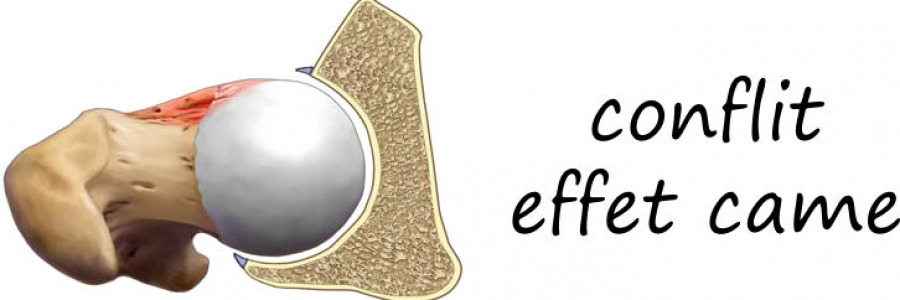

Classiquement il existe 3 formes possibles de conflits fémoro acétabulaires:

- par effet came: le facteur prédominant est l’excroissance osseuse de la face antérieure du col fémoral

Il s’y associe presque systématiquement toujours une déchirure du bourrelet cotyloidien (labrum tear).